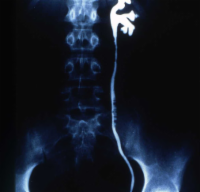

Die Behandlung umfasste neben der perkutanen, transluminalen Dilatation der A. renalis die systemische Behandlung mit Cortison und β-Blocker. Unter dieser Behandlung kam es zur Verbesserung der linksseitigen Nierenfunktion auf 30%. Das AUR zeigte eine zeitgerechte Kontrastmittelausscheidung (Abbildung 20). Im weiteren Verlauf ist evtl. eine neuerliche Dilatation erforderlich bzw. eine operative Versorgung der Nierenarterienstenose.